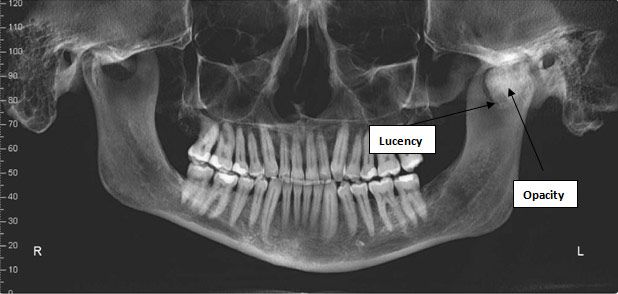

The panoramic radiograph revealed a large irregularly shaped opacity associated with the left mandibular condyle (Figure 1). At the inferior margin there appeared to be a small oval radiolucency. The anterior margin of the opacity was sharply defined, but the superior margin appeared to include an irregular surface contour. The mandible itself was slightly asymmetric, with the height of the left ramus appearing longer than the left. The dentition and bone otherwise appeared normal.

Figure 1